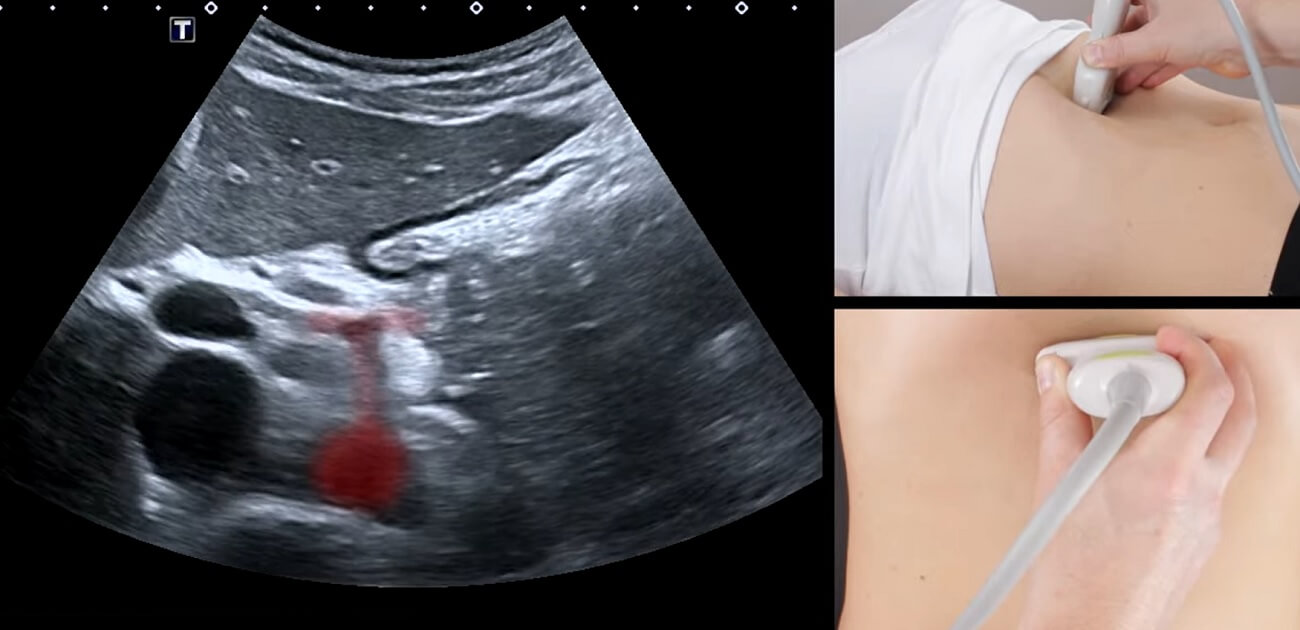

Ultrazvuk trbusne aorte je dijagnostički skrining test ili pregled koji koristi visoko-frekventne zvučne talase za kreiranje slika abdominalne aorte u realnom vremenu.

Za razliku od rendgenskih snimaka ili CT skeniranja, ultrazvuk abdominalne aorte ne koristi jonizujuće zračenje. Umesto toga, ova metoda se oslanja na zvučne talase koji se odbijaju od unutrašnjih struktura i pretvaraju se u slike prikazane na monitoru računara.

Ultrazvuk trbusne aorte omogućava lekarima da procene veličinu, oblik i strukturni integritet abdominalne aorte. S druge strane, dopler trbusne aorte procenjuje protok krvi kroz ovu arteriju.

Na abdomen (trbuh) pacijenta se nanosi providni gel na bazi vode.

Ovaj gel pomaže u eliminaciji vazduha između kože i ultrazvučnog transduktora (sonde), omogućavajući efikasno slanje i širenje ultrazvučnih talasa.

Lekar zatim pomera transduktor preko abdomena pacijenta.

Ovaj uređaj emituje zvučne talase koji prodiru u telo i reflektuju se od unutrašnjih abdominalnih struktura, uključujući trbušnu aortu.

Ovi reflektovani talasi se, potom, odbijaju (ultrazvučni “eho”) i pretvaraju u slike koje se u realnom vremenu prikazuju na ekranu računara.

Tokom ultrazvučnog pregleda aorte lekar pažljivo meri prečnik abdominalne aorte na više nivoa.

Posebna pažnja se posvećuje područjima gde se aneurizme često formiraju – obično ispod bubrežnih arterija.

Za procenu protoka krvi unutar aorte koristi se kolor dopler trbusne aorte, odnosno dopler abdominalne aorte.